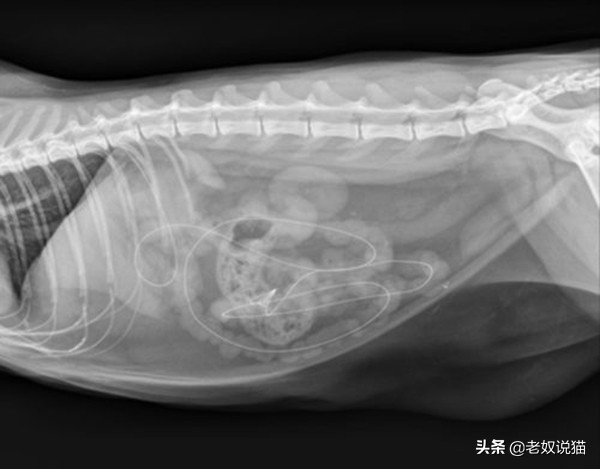

一、误食线类的东西

养猫的我们都知道猫猫很喜欢线,一根线能玩上一天,各种花样的玩,那么猫猫误食了多根线无法排出之后,经过就医在X光线下我们看到了哪些丢失的线,看后是何感想。

伊利诺伊州芝加哥市一只2.5岁的猫误食的吉他弦